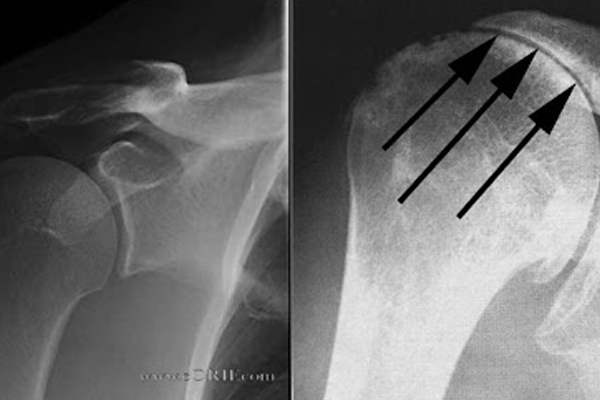

SHOULDER DISLOCATION